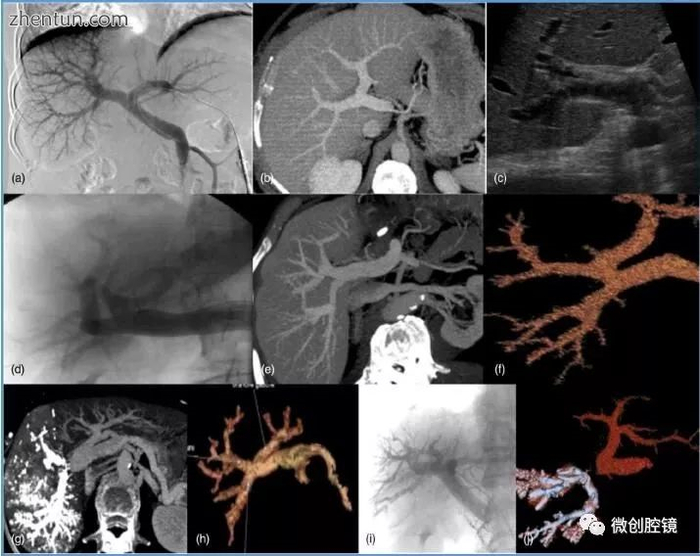

门静脉解剖结构的成像:(a)正常门静脉解剖结构的门静脉造影。(b)在正常门静脉解剖结构的门静脉期进行轴向增强计算机断层扫描(CT)扫描。(c)正常门静脉解剖结构的超声(US)。(d)1型门静脉解剖学的门静脉造影。(e)在1型门静脉解剖结构的门静脉期进行轴向增强CT扫描。(f)1型门静脉解剖结构的轴向3-D重建。(g)2型门静脉解剖结构的轴向增强CT扫描。(h)2型门静脉解剖的轴向3-D重建。(i)门静脉造影,3型门静脉解剖的轴向三维重建。(j)3型门静脉解剖学的轴向三维重建(图片由John Wiley和Sons从Charlotte Mouly,David Fuks,FrançoisBrowet,FrançoisMauvais,Arnaud Potier,Thierry Yzet,Qassemyar Quentin,Jean-Marc Regimbeau。右肝切除术中Glissonian法的可行性.HPP-国际肝癌胰胆管协会官方期刊.2013 15(8),638-645)(Mouly等,2013)。